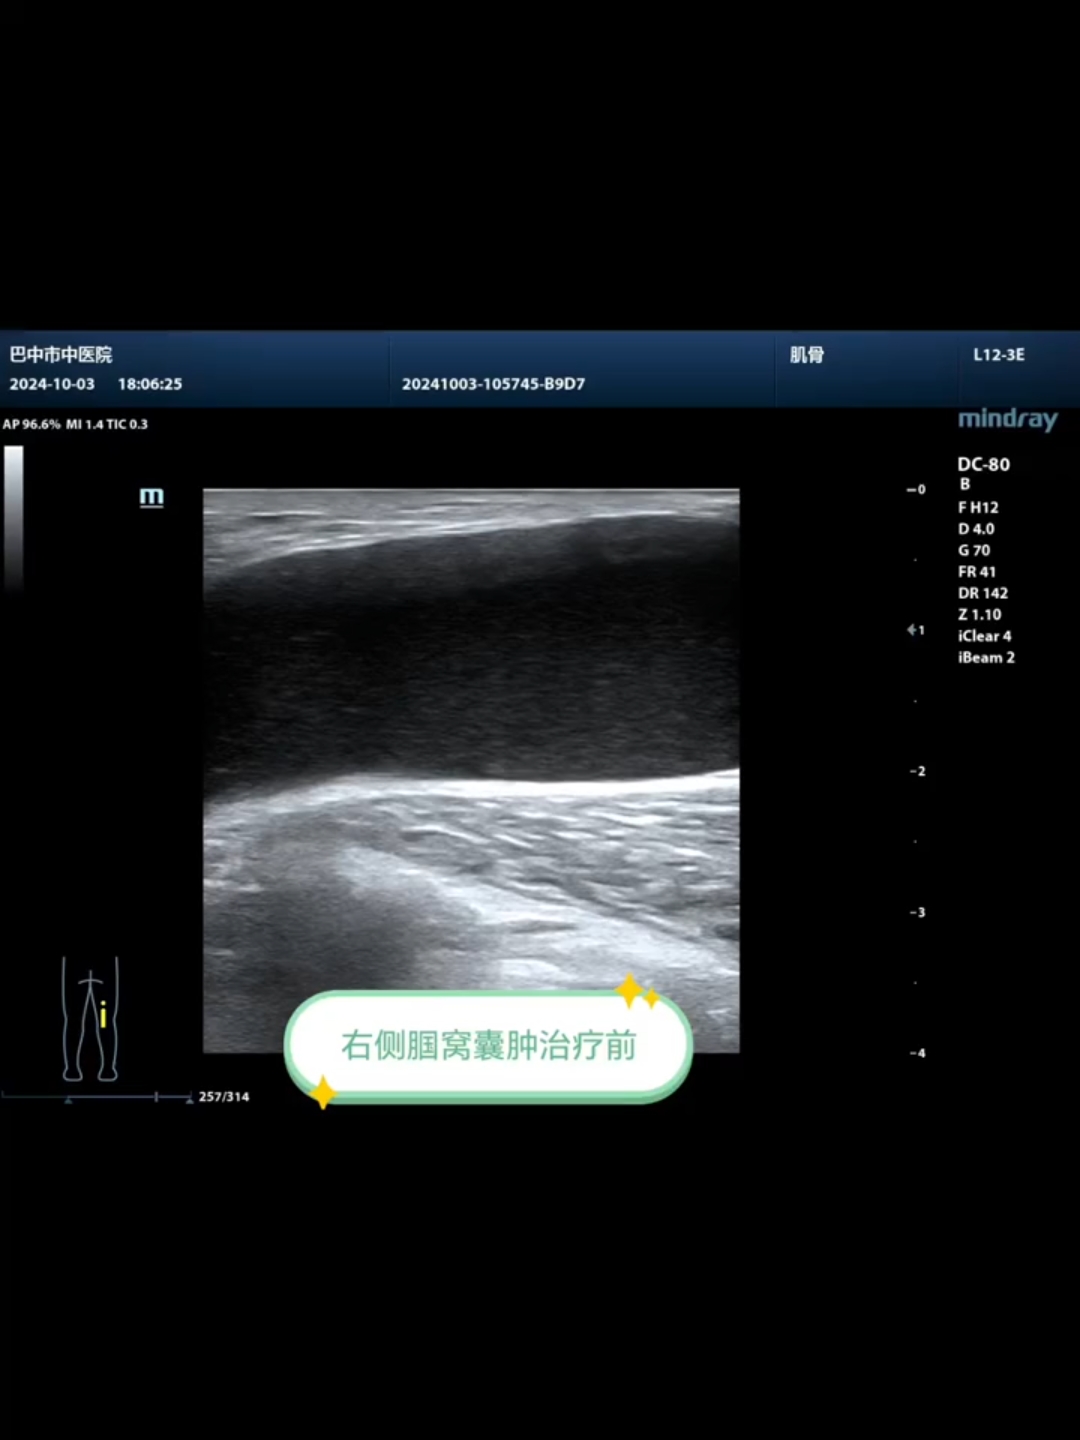

超声引导下腘窝囊肿硬化治疗

用户:超声介入治疗

超声下治疗腘窝囊肿

用户:骨科裴博士治疼痛

超声引导下治疗残余腘窝囊肿